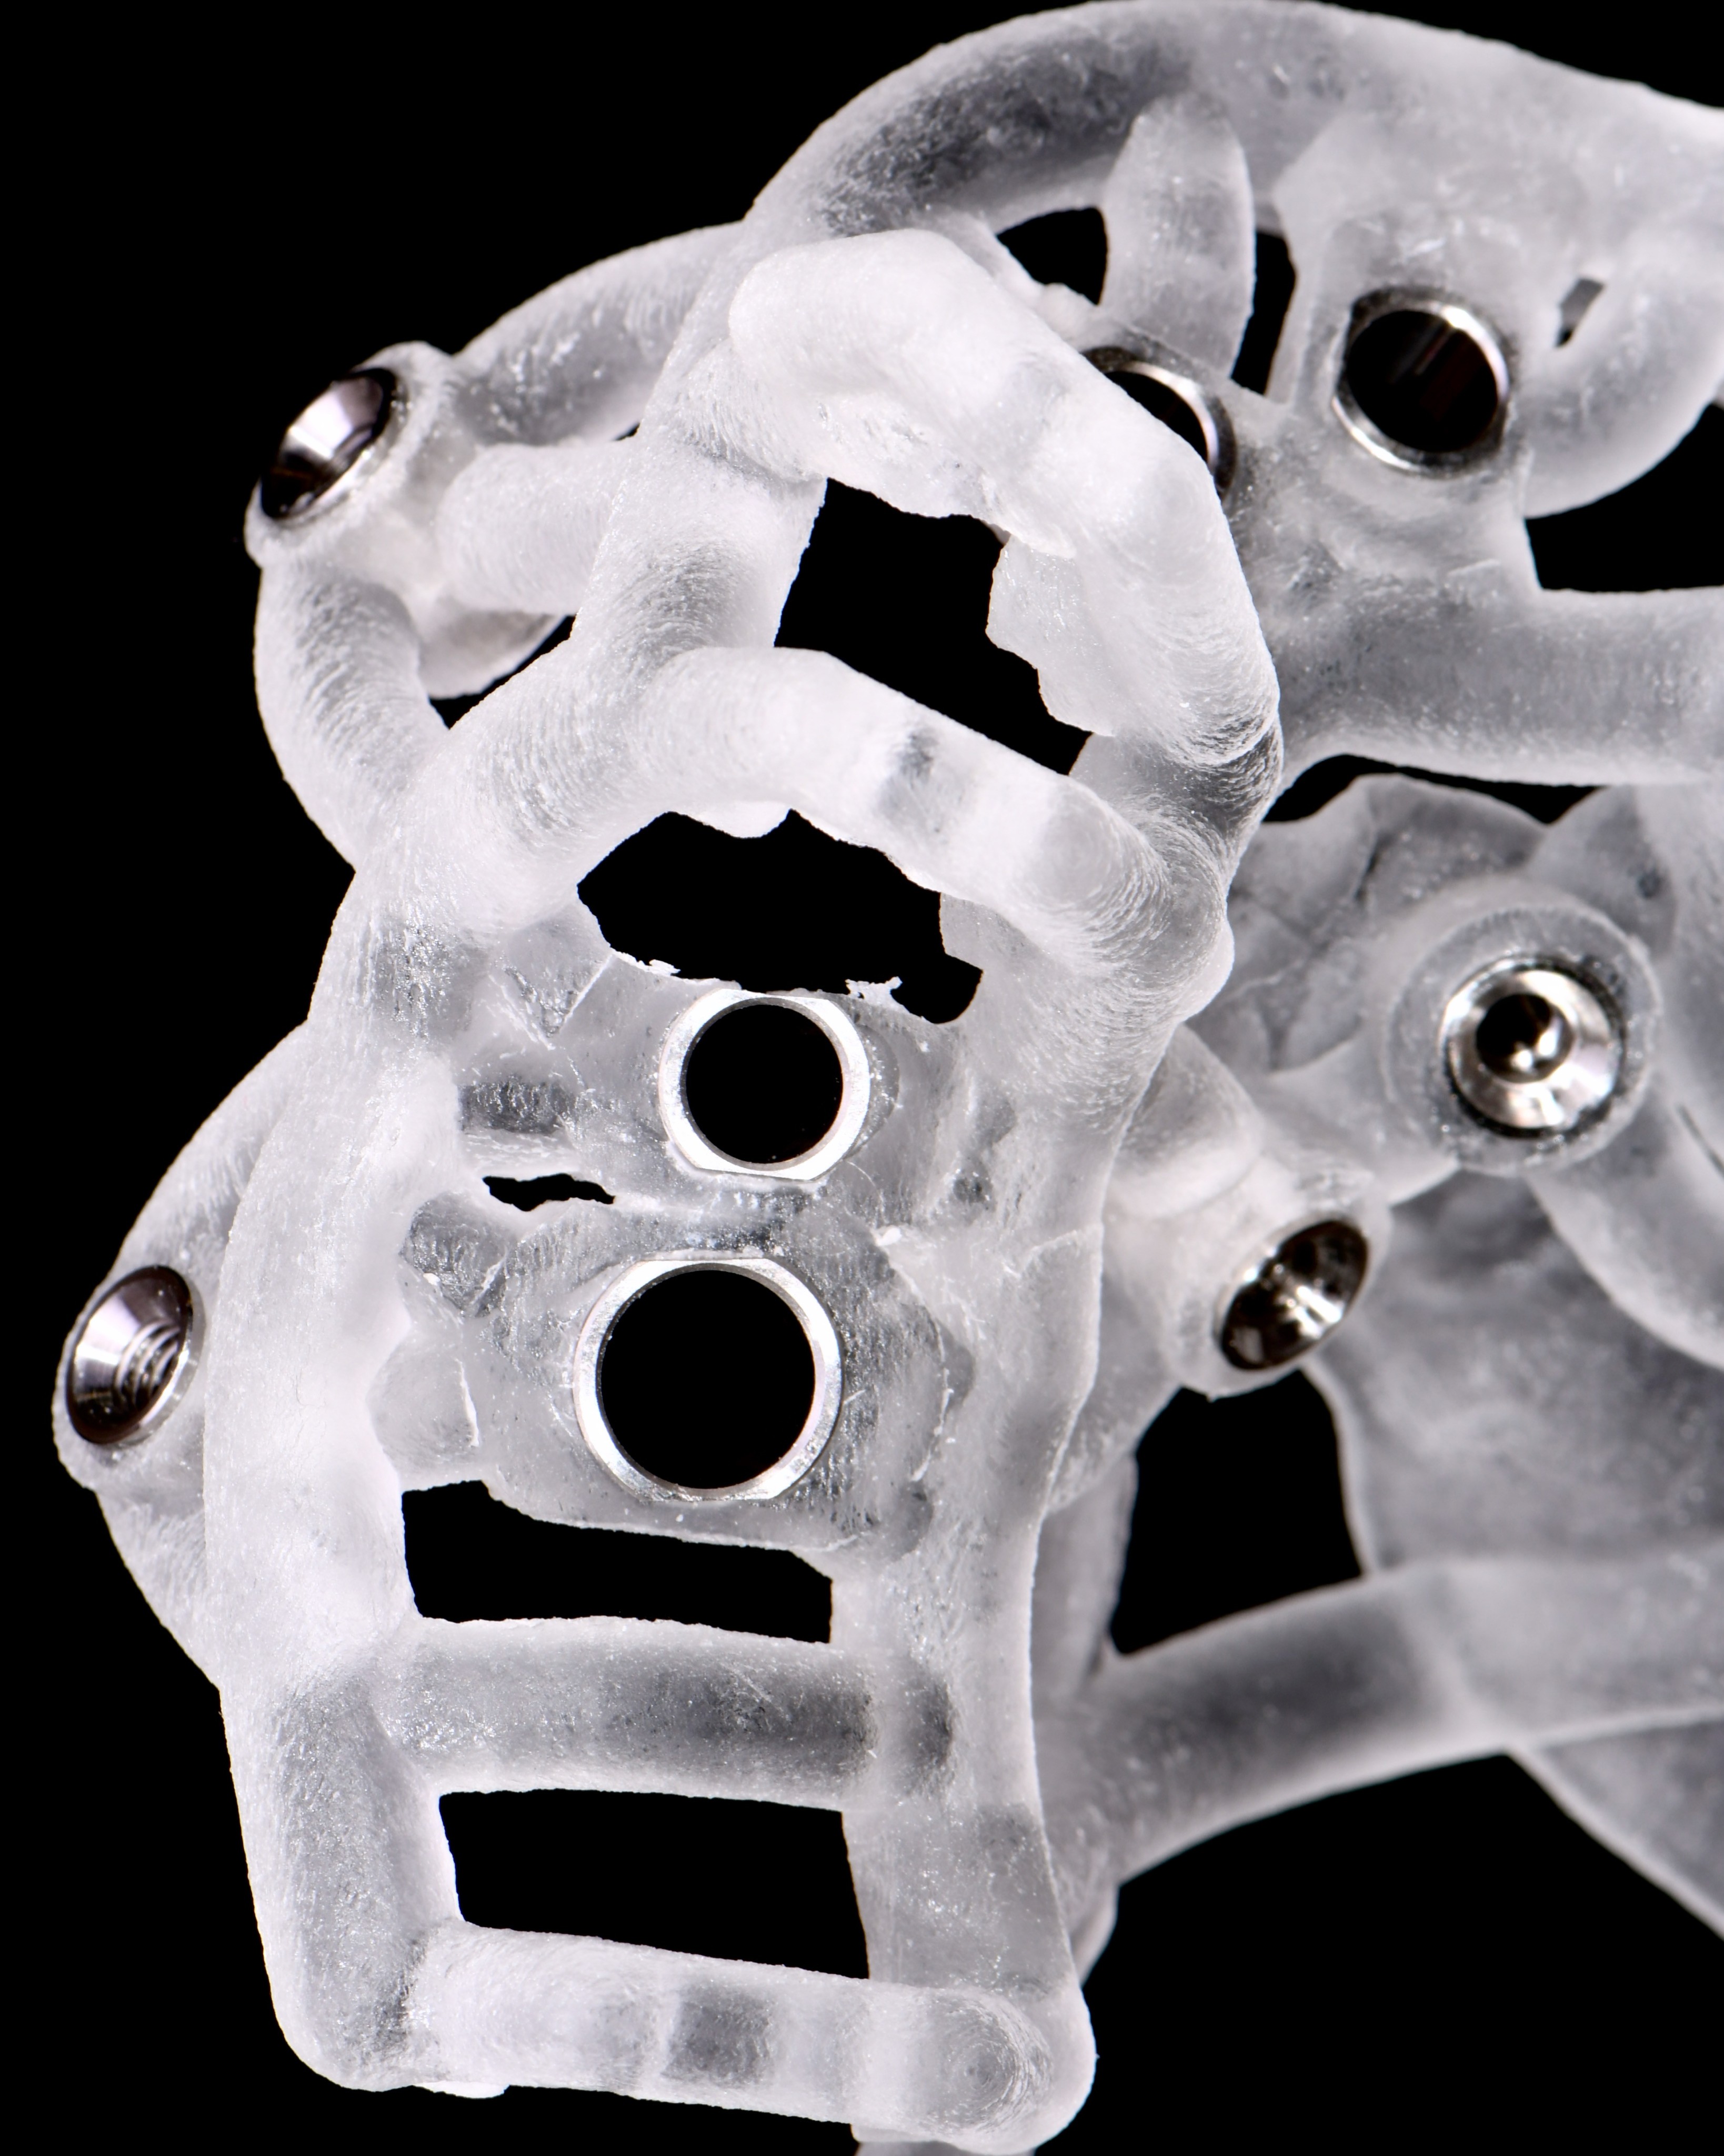

Qu’est ce que la chirurgie guidée et comment fonctionne-t-elle ?

La dentisterie moderne a connu une révolution grâce à des avancées technologiques. Les progrès ont transformé la manière dont les professionnels...

Voir plusLes avantages de la chirurgie guidée pour les patients

La chirurgie guidée en dentisterie représente une avancée significative qui va au-delà des aspects techniques pour offrir une expérience améliorée pour...